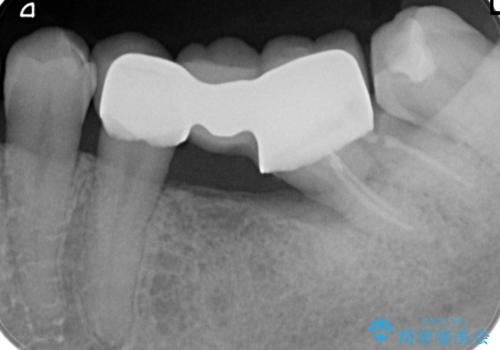

詰め物の外れてしまった奥歯 部分矯正で歯列を整えてから補綴治療